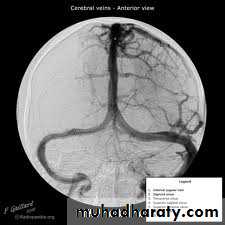

Cerebral angiography (the gold standard for evaluation of cerebral angiography) and can also demonstrate cerebral vasospasm

Angiographic vasospasm: asymptomatic arterial narrowing seen on angiography

Cerebral angiography